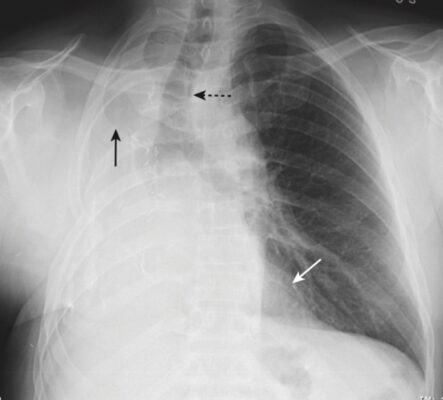

- Trở lại ca bệnh (anh S) với hình chụp X-quang phổi thẳng có mờ nửa phổi trái. Bất thường ở đây là gì?

- Hình ảnh cho thấy có sự dịch chuyển của tim và khí quản về phía phổi bị mờ (Hình 9). Đây là đặc điểm của xẹp toàn bộ một phổi. Do độ tuổi (31) và tiền sử mắc bệnh hen (bạn đã hỏi về bệnh sử), rất có thể là biểu hiện xẹp phổi do một nút chất nhầy gây tắc nghẽn.

- Anh S đã được chụp CT, cho thấy tắc nghẽn ở phế quản chính bên trái và nút nhầy sau đó đã được lấy ra bằng nội soi phế quản.